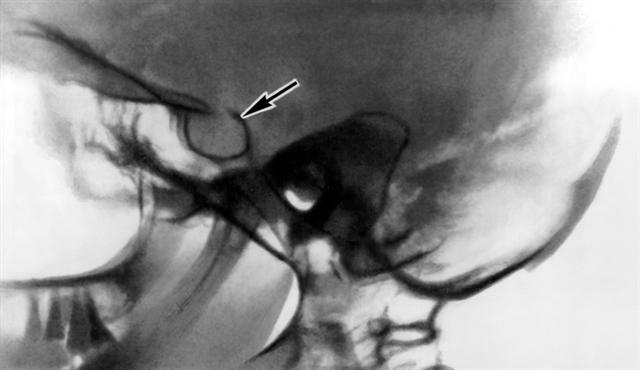

Рис. 1. Рентгенограмма черепа (боковая проекция) больной с макропролактиномой: видно значительное увеличение размеров турецкого седла (указано стрелкой).